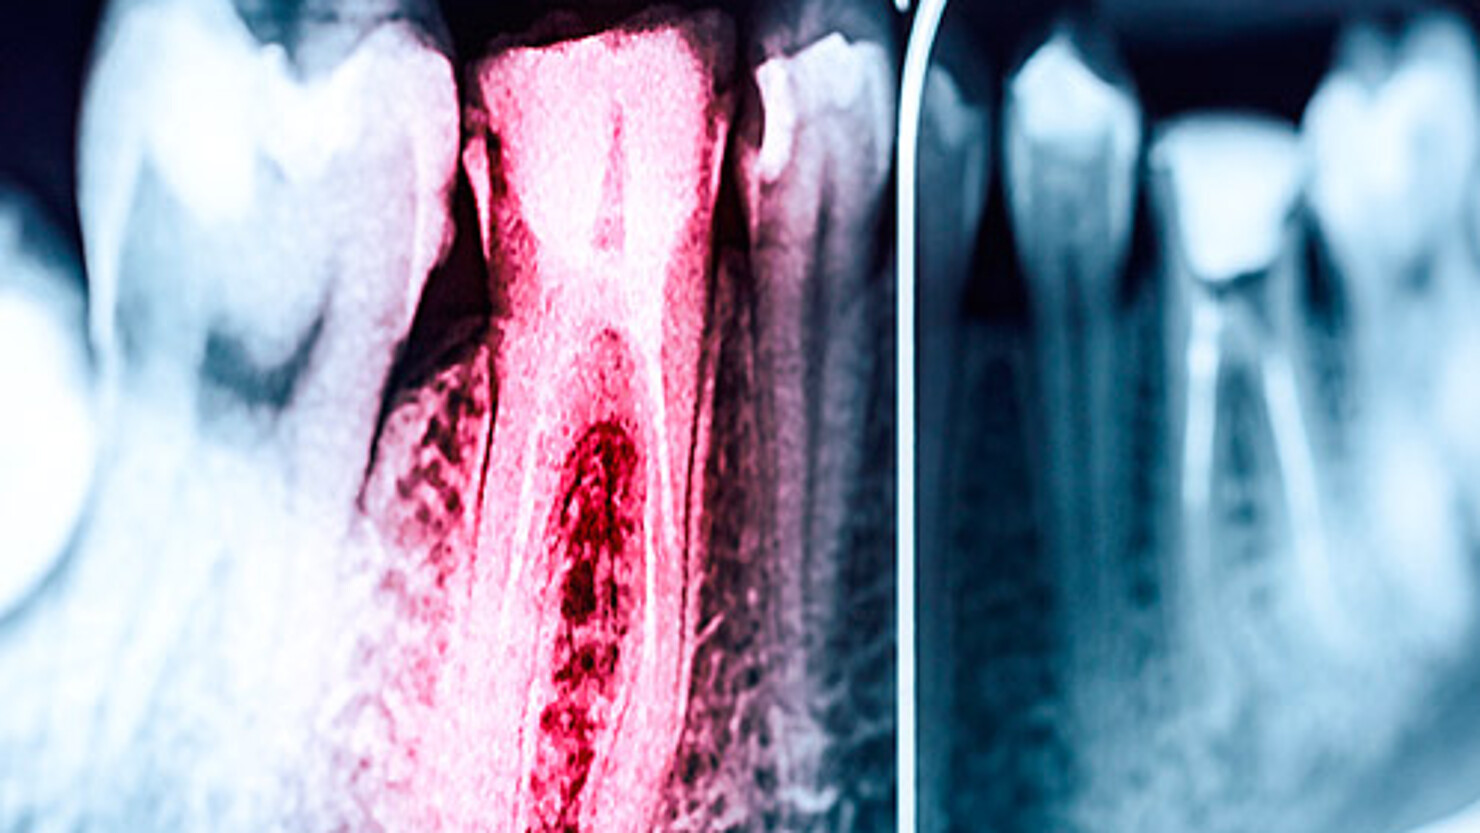

Eine Wurzelkanalbehandlung bedeutet, die Entfernung des irreversibel entzündeten oder abgestorben Endodonts (Zahnnerv) und chemische und mechanische Reinigung und Desinfektion der Wurzelkanallumens und dessen Bakterien dichten Verschlusses.

Hierfür gibt es mehrere Ursachen wie z.B. fortgeschrittene Karies, Zahnfrakturen, Traumata oder parodontale Schäden, durch die Bakterien bis zum Endodont vordringen können und eine Nervenentzündung auslösen.